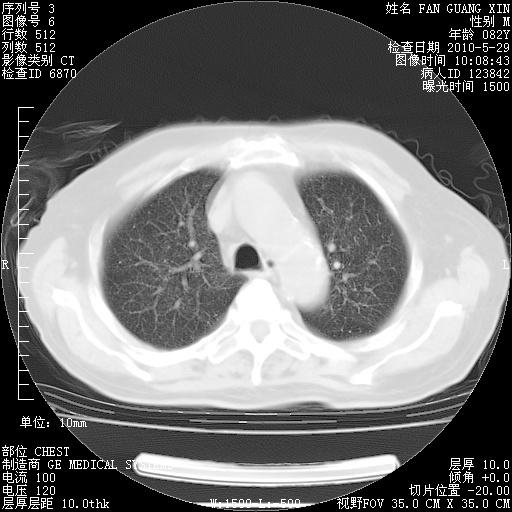

再治疗10天后的肺部CT 纵膈窗

阅读此次胸部CT,肺间质渗出性改变较入院时有吸收。目前从体温、白细胞、中性分叶明显增高,肯定存在细菌感染(发生医院感染哦,若无消化道及泌尿系统等感染的依据,肺部感染可能大)。若你院头孢哌酮舒巴坦钠耐药率较高,同意你的方案,若48小时体温仍高,可考虑使用碳青霉稀类抗菌药物,同时可予超声雾化、注意滴数时加大液体量。白蛋白33.30g/L较低哦,需加强营养等支持治疗。